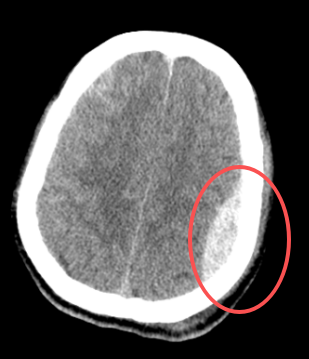

复查结果显示